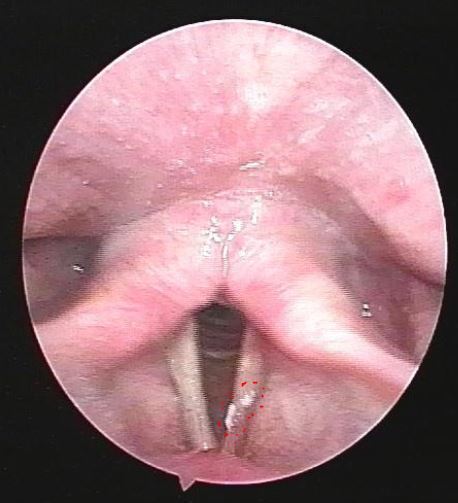

聲帶上的白斑是什么,這次徹底搞明白了

最近來自江西贛州的葉先生,53歲了。半年前咳嗽后出現(xiàn)咽部異物感,伴刺激性咳嗽,無伴聲嘶,咳嗽后發(fā)聲費力,無伴反酸、燒心感,無呼吸困難、吞咽障礙,在外院行喉鏡檢查提示“左側(cè)聲帶腫物”,藥物治療后效果一般,今為進一步診治。檢查后發(fā)現(xiàn)聲帶上有白斑,這種情況建議手術(shù)切除。入院后安排了全麻聲帶腫物切除術(shù),插管全麻后在內(nèi)鏡下切除聲帶的白色腫物,組織送病理檢查,發(fā)現(xiàn)是鱗狀上皮伴輕度不典型增生。這種情況一般需要戒煙、戒酒,防止病變繼續(xù)發(fā)展成為腫瘤。關(guān)于聲帶腫物,如果您還有什么問題,歡迎留言和耳鼻喉鄭立崗醫(yī)生進一步交流。